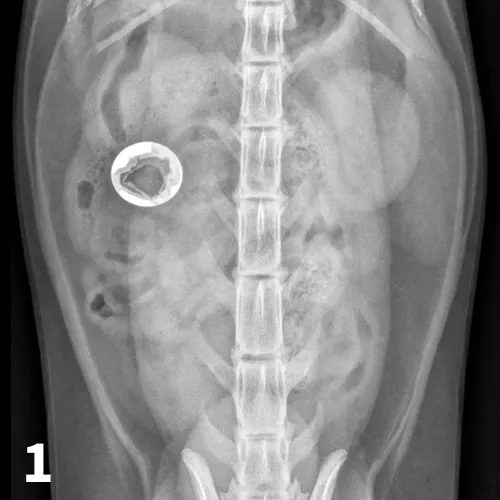

In cases of suspected FBs, this technique can be helpful to differentiate dilated small intestinal loops from colon or determine whether mottled mineralized material is in the colon or small intestinal tract. After initial survey radiographs are taken (Figures 6A and 6B), the animal is placed in lateral recumbency. Air is instilled into the rectum and colon using a large lubricated syringe or rubber catheter; approximately 10 to 12 mL/kg of air is needed for moderate distention of the colon.6,7 Standard lateral and ventrodorsal radiographs are then taken (Figures 6C and 6D). In most animals, it is desirable to fill the colon to the cecum. Partial filling of the distal jejunum and ileum may occur and is normal.

FIGURE 6A

Left lateral (A) and VD (B) survey radiographs of a 4-year-old pit bull terrier with a 3-day history of vomiting, diarrhea, and anorexia. A dilated loop of bowel is present within the midabdomen (star) caudal to the stomach, which could represent large or small bowel.